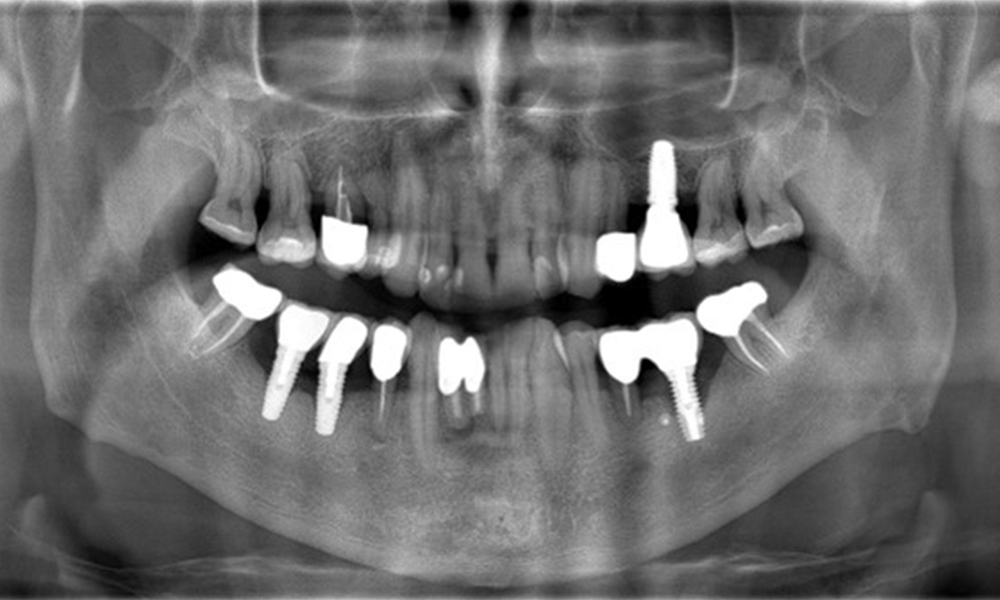

A 52-year-old patient presents at a preventive care session. The patient has no systemic disease and is not taking any medication. He has had various dental treatments and also has two active carious lesions. In addition, the patient has four implants (2nd, 3rd and 4th quadrants). He is revealed to have early periodontal disease (stage IV, grade B). His periodontal condition is stable; a probing depth of Probing depths (ST) of 5 mm is only evident at the implant in region 36. Gingivitis is also identified.

The patient has no particular risk factors with specific dental implications in his medical history. The key factor, therefore, is the requirement in terms of oral health. In this respect, there is evidence of a probing depth of 5 mm at the implant in the 3rd quadrant and, on the X-ray image, increased bone loss. The patient also has currently stable early periodontal disease and two active initial carious lesions.

The X-ray images show the progression of bone loss.

The X-ray images show the progression of bone loss. OPG from 29.06.2020 (left) and OPG from 26.02.2024 (right).

The X-ray images show the progression of bone loss in the area of the implant in region 36: dental film from 11.02.2021 (left) and dental film from 18.01.2024 (right).